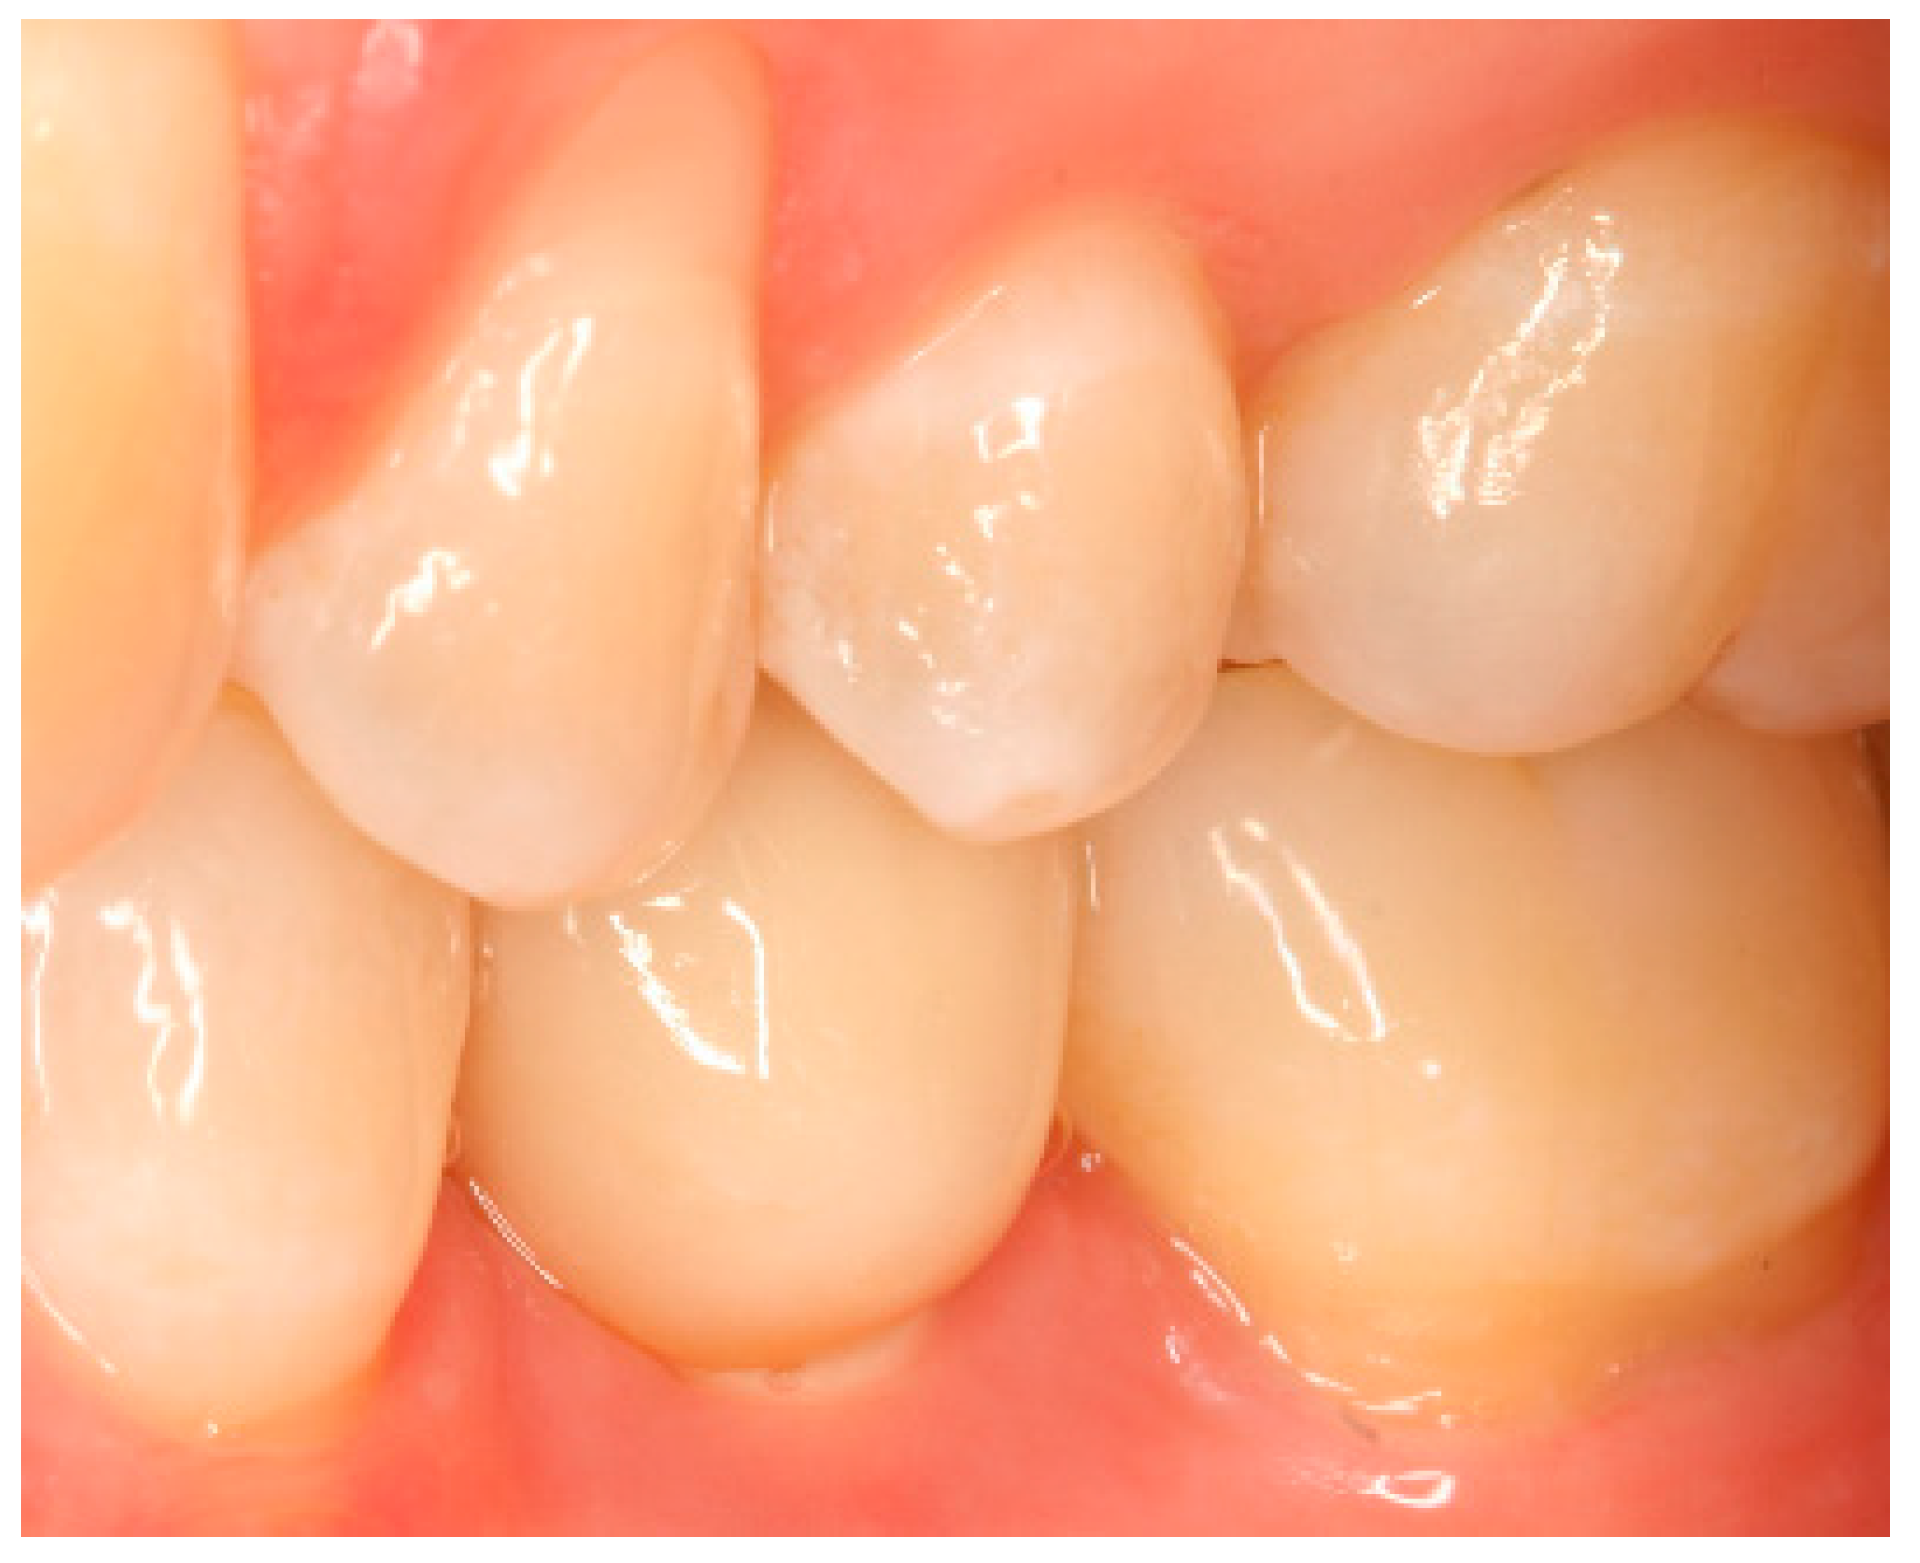

Appendix B. Exemplary Photographs and Radiographs from a Patient at Different Examination Time Points and a More Negative Outcome